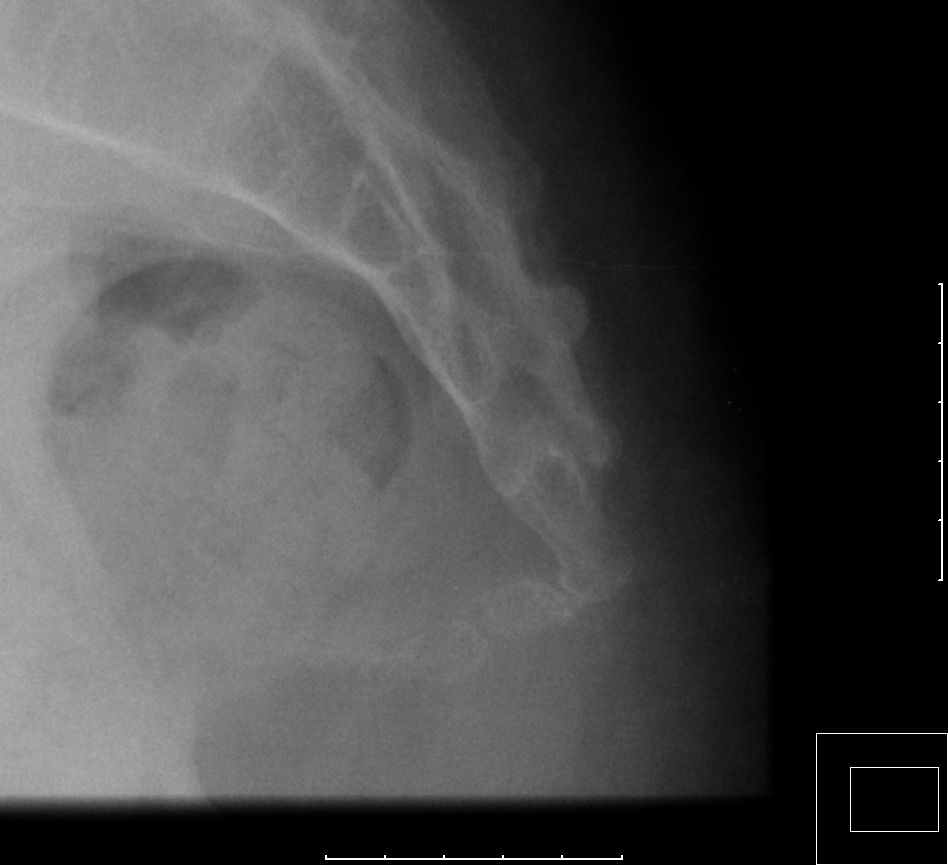

| Beckenschaufel | 65-jähriger Mann, der bei schwerer

Anämie infolge Magenkarzinom auf die linke Seite gestürzt ist. Das CT zeigt

einen Abbruch der Darmbeinschaufel.![]() |